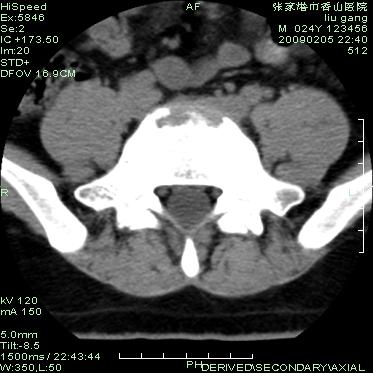

以下是引用随光逐影在2009-3-11 14:43:00的发言:[br]平片:l3、4、5及s1前上缘见类似“切角征”。[br]ct扫描:腰椎多个节段椎间盘向椎体内(椎体前部)突出。